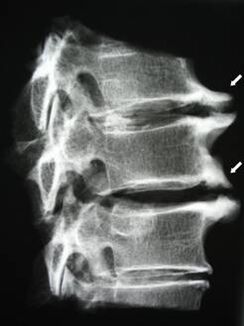

Στα αρχικά στάδια, η οστεοχόνδρωση ανιχνεύεται με μαγνητική τομογραφία. Αργότερα, η παθολογία μπορεί να διαγνωστεί χρησιμοποιώντας ακτινογραφία. Στις ακτινογραφίες της αυχενικής μοίρας της σπονδυλικής στήλης, η μείωση της απόστασης μεταξύ των σπονδύλων, οι παθολογικές αλλαγές στις αρθρώσεις της όψης και η οστεοφυτία γίνονται αισθητές.